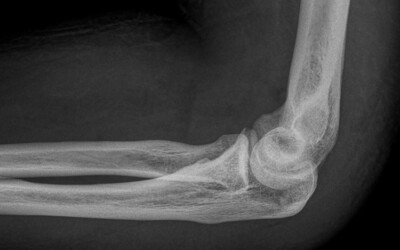

Tennis elbow or epicondylitis

Created:02-11-2012 || Updated: 07-02-2020

Golfer's elbow or epitrocleitis

Created:19-01-2013 || Updated: 07-02-2020